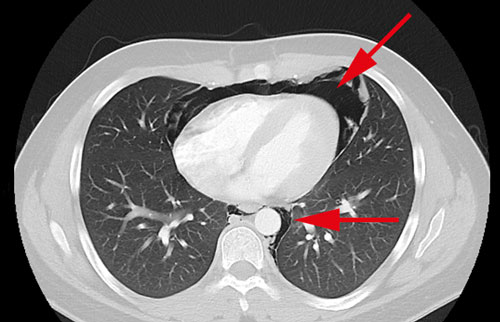

En översiktlig ultraljudsundersökning av hjärtat gjordes bedside för att se eventuell perikardvätska. Patientens hjärta var svårundersökt med ultraljud och kunde inte visualiseras i sin helhet, vilket är ovanligt hos en yngre normalbyggd man. Någon tydlig perikardvätska kunde dock inte påvisas. Blodprov visade normala värden för troponin T, CRP och LPK. För att utesluta pneumotorax gjordes lungröntgen som visade en luftspalt i mediastinum och kring hjärtat, fynd som vid pneumomediastinum och pneumoperikardium (Figur 1). I syfte att utesluta framför allt esofagusruptur som orsak till pneumomediastinum undersöktes patienten med datortomografi av torax med intravenös och peroral kontrast. Även denna undersökning visade luft i mediastinum och perikardiet. Inga tecken till kontrastläckage från esofagus eller andra patologier kunde påvisas (Figur 2–4). Luften kring hjärtat bedömdes förklara svårigheten att undersöka hjärtat med ultraljud. Mot bakgrund av anamnes och radiologiska fynd ställdes diagnosen spontan pneumomedia­stinum och pneumoperikardium. Ingen ytterligare akut utredning bedömdes nödvändig. Han överflyttades till toraxkliniken vid Karolinska universitetssjukhuset för fortsatt observation och smärtlindring. Han förbättrades snabbt och skrevs ut 3 dagar senare, och vid telefonuppföljning efter en månad var patienten helt återställd.

Figur 4. Datortomografi av torax med intravenös och peroral kontrast visar luftstrimmor i övre mediastinum kring aortabågen, trakea och esofagus.